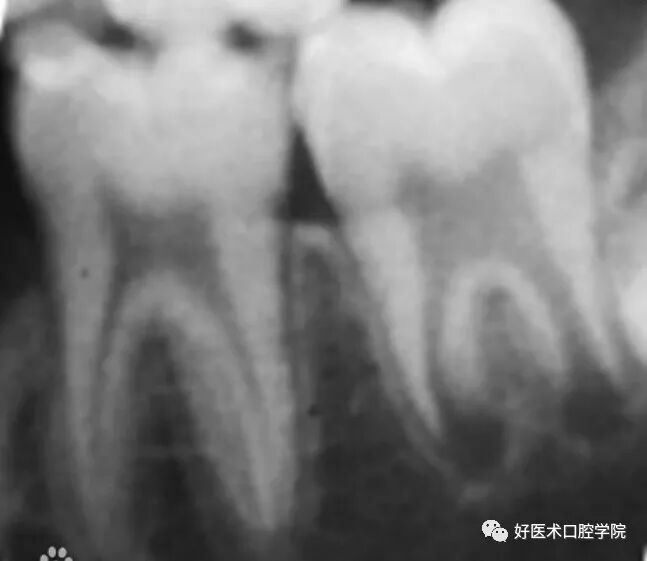

所示为成熟恒牙(左侧)与年轻恒牙(右侧)的X线片

1960年Nolla将X线片上的年轻恒牙钙化过程分成了10个阶段,称为Nolla分期,现在已成为临床评估牙齿发育程度的常用参考指标。